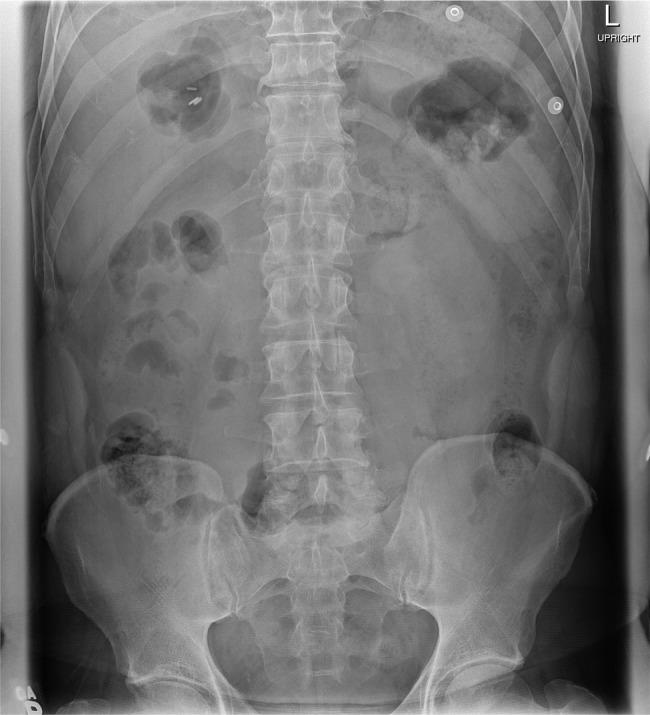

Bowel perforation is a rare complication of laparoscopic cholecystectomy, which if left undiagnosed can have fatal consequences. In addition, isolated small bowel perforation is extremely rare and should be considered in patients presenting with sudden onset abdominal pain in the postoperative period. A 57-year-old male with symptomatic gallstones underwent urgent laparoscopic cholecystectomy and was discharged home on postoperative day (POD) 1 without complications. He presented to the emergency department on POD 11 complaining of sudden onset abdominal pain. A CT scan did not confirm a diagnosis and he was admitted for observation. On post admission day 2, he became significantly peritonitic and laparotomy revealed jejunal perforation. Bowel resection with hand-sewn anastomosis was completed and he was discharged on POD 10. Follow-up at 6 weeks revealed no further issues. We review the literature on small bowel perforation post laparoscopic cholecystectomy.

肠穿孔是腹腔镜胆囊切除术罕见的并发症,若未被诊断,可能会导致致命后果。此外,孤立性小肠穿孔极为罕见,对于术后突发腹痛的患者应予以考虑。一名57岁有症状胆结石的男性接受了急诊腹腔镜胆囊切除术,术后第1天出院,无并发症。他在术后第11天因突发腹痛就诊于急诊科。CT扫描未确诊,遂住院观察。入院第2天,他出现明显的腹膜炎,剖腹探查发现空肠穿孔。完成肠切除并手工缝合吻合,他于术后第10天出院。6周后的随访未发现进一步问题。我们回顾了腹腔镜胆囊切除术后小肠穿孔的相关文献。